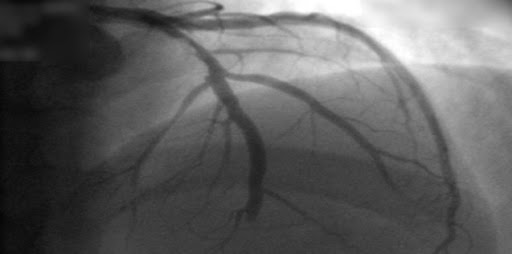

Antiagregación dual abreviada después de la colocación de un stent coronario en pacientes con alto riesgo de sangrado

Un mes de terapia antiplaquetaria dual no fue inferior a la continuación por dos o más meses adicionales con respecto a la aparición de eventos clínicos adversos netos y eventos cardíacos o cerebrales adversos mayores, pero logró una menor incidencia de hemorragias clínicamente relevantes. New England Journal of Medicine, 28 agosto de 2021.